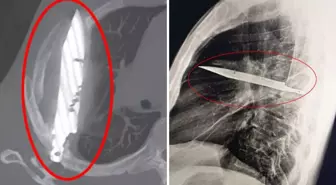

Tanzanya‘da 44 yaşındaki bir adam, sağ memesinin altından iltihap akması şikâyetiyle hastaneye gitti. Doktorlar ilk muayenede herhangi bir ağrı, nefes darlığı, öksürük ya da ateş bulgusuna rastlamadı. Ancak yapılan röntgen, herkesin ağzını açık bıraktı: Adamın göğsünde tam sekiz yıldır saplı duran bir bıçak vardı.

Hasta, yıllar önce yaşadığı şiddetli bir kavga sırasında yüzünden, sırtından, göğsünden ve karnından yaralandığını, o zaman tedavi gördüğünü söyledi. O günden beri ciddi bir sağlık sorunu yaşamamıştı. Fakat son günlerde fark ettiği iltihap nedeniyle doktora başvurunca, yıllardır göğsünde “unutulmuş” bıçak ortaya çıktı.

Bıçak, sağ kürek kemiğinden girip hayati organlara zarar vermeden göğüste kalmıştı. Ameliyatla çıkarılan bıçakla birlikte ölü doku temizlendi. Hasta yoğun bakımda bir gün, normal serviste ise 10 gün kaldı. Doktorlar, takip kontrollerinde hastanın tamamen iyileştiğini duyurdu.